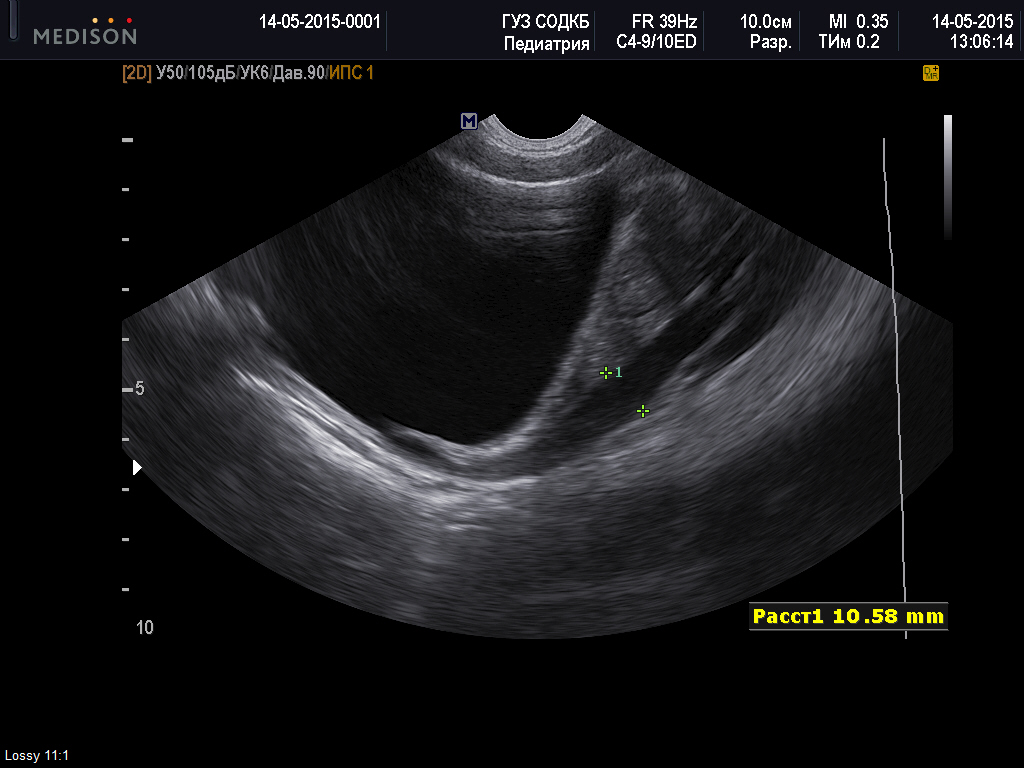

Один из мочеточников слева расширенный на фоне диуретика